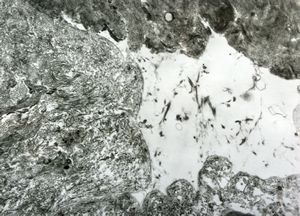

M, 40y. | unclassified skin inflammation … alterated collagen

M, 40y. | unclassified skin inflammation … phagocytosed of collagen